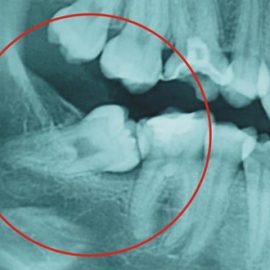

Encías sanas, cavidad bucal contenta

Unas encías sanas te permiten evitar esa apariencia inflamada y rojiza en la boca que podría avergonzarte al sonreír, además del dolor que ocasiona esta condición y el sangrado que produce al cepillarnos. Debes saber que una de las principales causas de la pérdida de dientes es la enfermedad en las encías o gingivitis. Pero Read More